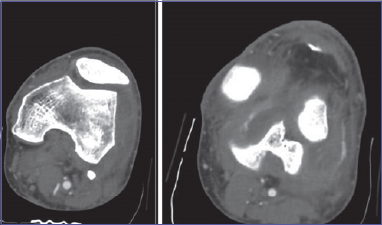

On inspection, the knee was swollen, an anatomical deformity with 90° knee flexion was noted. The patient did not complain of paresthesia or sensory deficits. The limb was warm and with palpable pulses. X-ray exam showed a PL knee dislocation (Fig. 1). Closed reduction and immobilization with posterior brace were performed, under conscious sedation, in the emergency department. Neurovascular status was closely monitored. Angio-CT scan was performed to exclude vascular injuries (Fig. 2). The patient was hospitalized. Neurovascular status, skin condition and clinical parameters were strictly monitored. The knee was unstable with persistent PL subluxation, worsened by dyskinesias, and both varus and valgus instability. The lesion was classified as a grade IV KD of Knee Dislocation Classification System. A staged multi-ligament reconstruction in two steps was planned: acute reparation of MCL and LCL and a staged reconstruction of both ACL and PCL. A neurologist was consulted to optimize the patient’s therapy with the aim of reducing the risk of recurrence. After 3 days we performed an acute surgical reparation of both the MCL and LCL. A 30° locked knee brace was placed. Postoperative X-rays exam (Fig. 3) showed perfect knee reduction. On the fifth postoperative day the patient was discharged with home care and an outpatient controls program. We planned to unlock the brace after 25 days, check the ligament status and then perform a knee MRI in order to plan an ACL-LCL reconstruction within 2 months. After 25 days, patient came to the outpatient department to unlock the brace. We noticed a relapse of PL subluxation with varus-valgus instability and failure of the MC and LCL reparation. The main causes of failure were the persistent and violent dyskinesias, due to Parkinson disease. In this context, plan a staged reconstruction would have been at high risk of another ligament failure. Thus, we talked with patient, and changed the strategy. Three months after the injury the patient was hospitalized and underwent, in general anesthesia, a total knee replacement with a hinged prosthesis (Fig. 4). We choose a hinged prosthesis to make the implant as stable as possible to resist dyskinesias. Postoperative anemia was observed, requiring the transfusion of 2 concentrated red blood cell units. No other postoperative complication was observed. From the day after surgery the patient started active and passive mobilization of the knee and a re-education protocol with full weight bearing. The patient was discharged on the 7th postoperative day to continue rehabilitation. Clinical and radiographic controls were performed at 3, 6, 12 months and then annual follow-up. At the last follow-up (3 years) the patient was walking without crutches, with full ROM, no pain and the same level of activity as before the injury (Fig. 5).

Figure 2.Angio CT scan at emergency department.